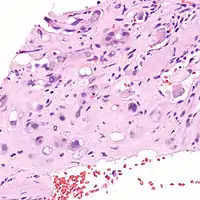

| Micrograph of an epithelioid hemangioendothelioma of the liver. | |

EHE is a soft tissue sarcoma and is generally considered a vascular cancer insofar as the ‘lesional’ cells have surface markers typical of endothelial cells (cells lining the interior of blood vessels). EHE was originally described as occurring most commonly in the veins of the extremities (arms and legs) and two organs, the liver[2] and lungs. It has since been described in organs throughout the body. In addition to liver and lungs, bones and skin have been the most frequent organs.